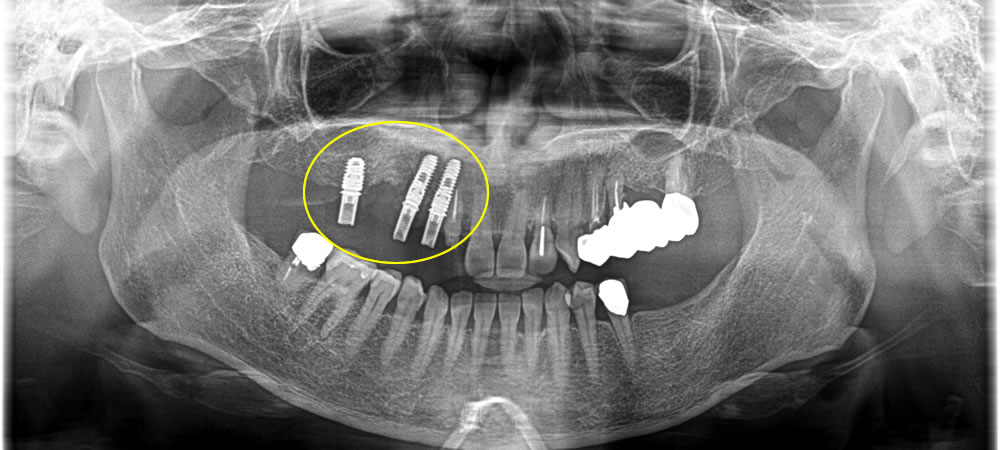

インプラント埋入手術の実施

ブリッジの手前の歯はまだ使うことができると判断し、ブリッジ除去後、一本のかぶせ物にしました。奥の歯は抜歯後、下の歯と奥まで噛み合うように設計し、金額を抑えるため、本来4本分の歯をいれるところをインプラント3本でブリッジにし、4本分の歯を作りました。奥の歯は骨の損傷が大きかったため、抜歯と同時に骨造成も行っています。

上部構造の装着・治療完了

完成した上部構造(ブリッジ)を装着し、咬み合わせを調整して治療完了です。

術前は右下奥の歯が噛み合っていませんでしたが、術後は奥まで噛み合うようになり、奥まで均等に噛み合うことで全体の歯の負担を減らすことができます。術前よりもものがしっかりと噛めるようになり、審美的にも機能的にも大変満足していただくことができました。